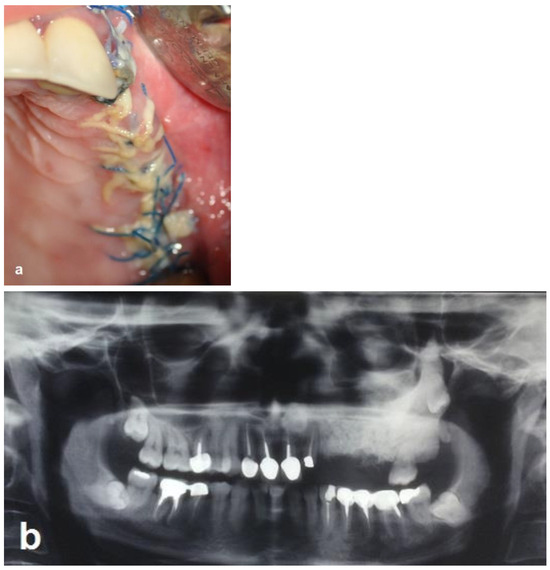

Figure 4. Intraoperative views. (a) Bone ostectomies in a box shape were carried out while preserving the buccal and palatal bone walls. No bleeding was observed. (b) Decortications of the box walls including the maxillary sinus bony floor were performed to enhance bleeding. (c) Grafting the box with particulate bone substitute. (d) PBFPG was utilized to enhance blood supply to the bone graft. (e) Primary closure of the flap with absorbable sutures.

The bone surgery was performed in the outpatient clinic under sterile conditions with intravenous sedation and local anesthesia. A midcrestal incision was performed at the edentulous ridge, with the envelope flap at the first molar. Anterior and posterior vertical releasing incisions were made, followed by buccal elevation of the flap. The first molar was removed. A box with dimensions of 2 cm anteroposterior and 1 cm bucco-palatal was outlined for bone evacuation, with the depth of the box limited by the floor of the maxillary sinus. Thin buccal and palatal walls were preserved. The bone ostectomies were performed with straight and round surgical burs. A marble bone quality without bleeding was noticed during the ostectomy (Figure 4a). The floor of the sinus was located 20 mm from the crest. Bleeding was induced by making small perforations in the bony floor of the maxillary sinus with a small round surgical bur (Figure 4b). Additional deep decortications were made in the palatal and buccal walls of the box. After completion of these procedures, particulate bone substitute (Bio-oss, Geistlich, Switzerland) was grafted and packed into the box (Figure 4c). Periosteal releasing cuts were made in the inner side of the mucoperiosteal flap in order to achieve soft tissue closure. In addition, a pedicled buccal fat pad graft (PBFPG) was obtained from the left buccal fat pad that was accessed through the distal vertical releasing incision. The PBFPG enhanced the soft tissue primary closure of the grafted box and served to provide blood to the compromised operated area (Figure 4d,e). Suturing of the treated site was performed using absorbable sutures (Vicryl 3/0, Peters Surgical, France).